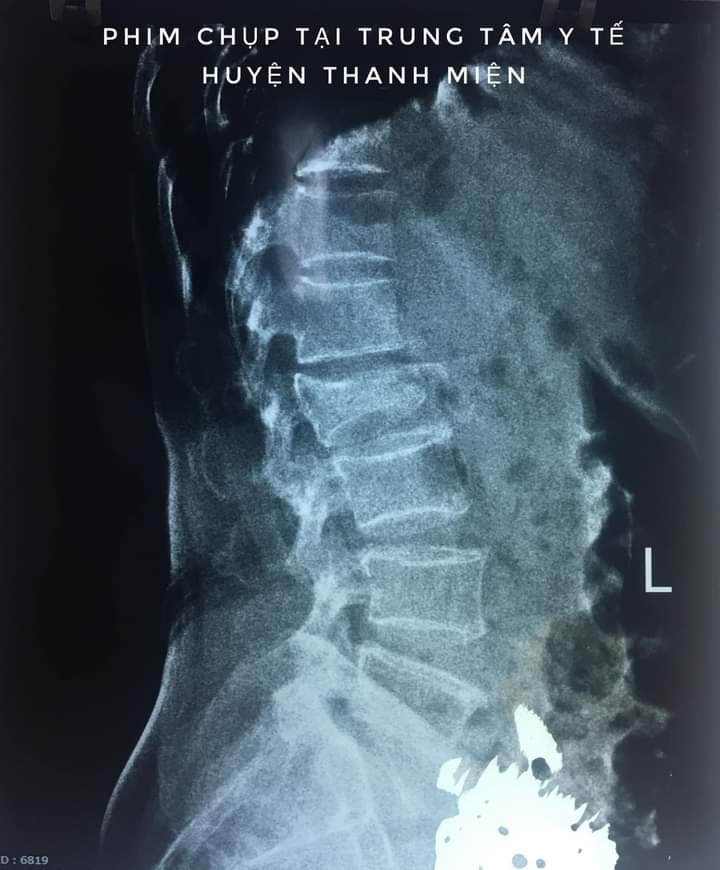

Anh Q vào viện do ngã cây vải đau nhiều cột sống thắt lưng, liệt hoàn toàn 2 chi dưới đã được các bác sĩ khoa cấp cứu BVĐK Tỉnh Hải Dương khám, cố định cột sống, chụp chiếu chẩn đoán CTCS gãy D12 L1 mất vững Frankel A , a đã được các bác sĩ hội chẩn và được các bác sĩ khoa ngoại 2 Phẫu thuật cấp cứu làm vững cột sống, giải ép tủy, khâu phục hồi màng tủy. Sau 10 ngày điều trị hiện tại sức khỏe của anh Q ổn định và được tập phục hồi chức năng, tuy đã phẫu thuật nhưng do tổn thương của anh Q phức tạp tổn thương tủy sống nên sự hồi phục vận động và cảm giác của a Q rất chậm và cần phải có một thời gian rất dài.